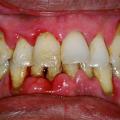

Фото 2. Гнойное воспаление дёсенного кармана на тяжелой стадии. На десне образуется язва.